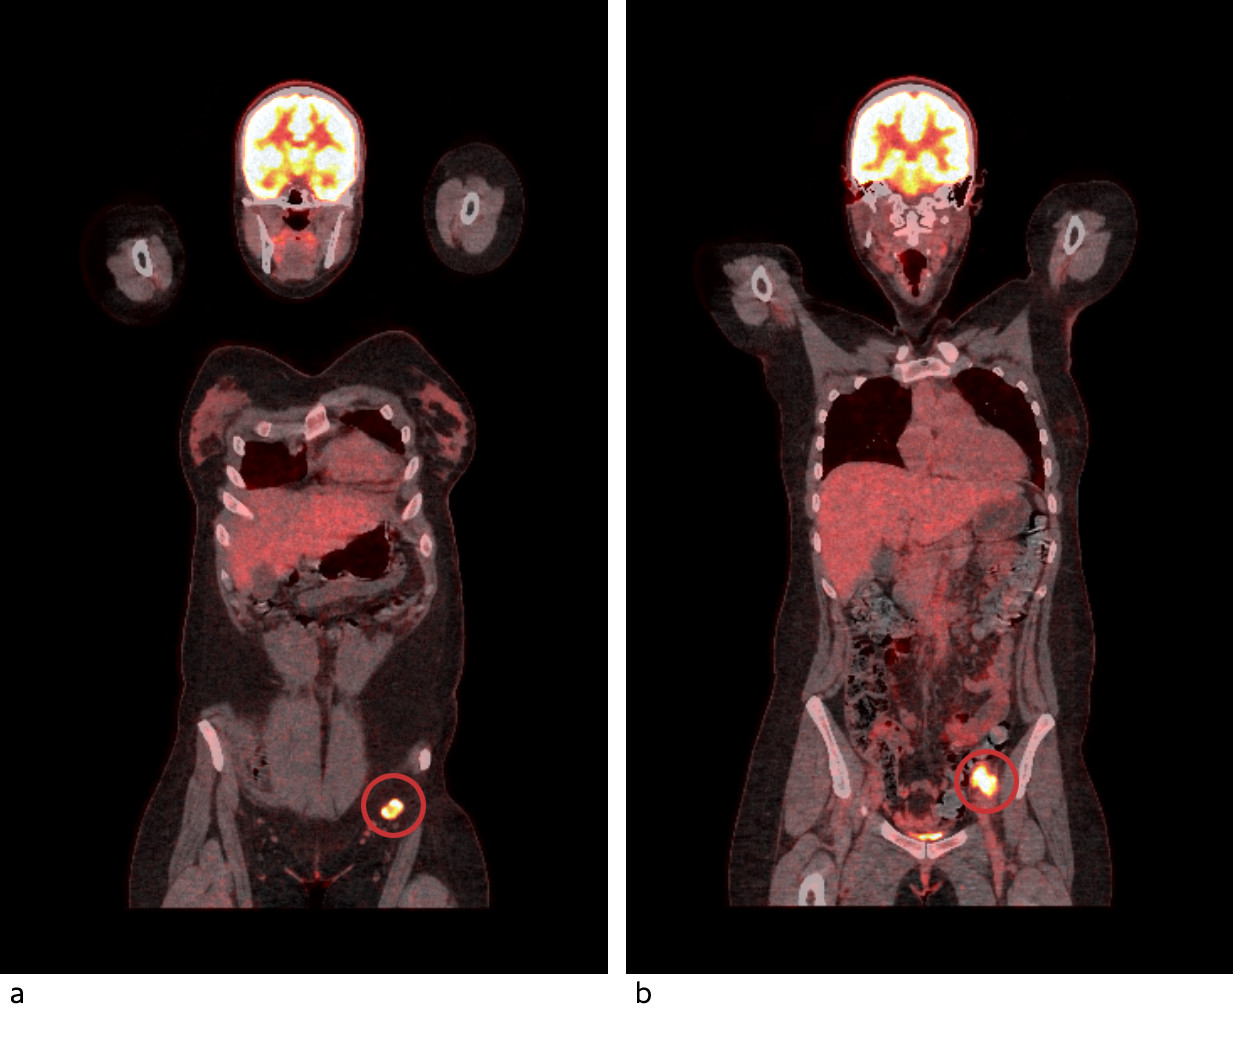

Halvannen uke etter utskrivning fra revmatologisk avdeling ble det gjort PET-CT, som viste lett til moderat opptak av 18F-fluorodeoksyglukose (FDG) i begge lunger i kjente subpleurale fortetninger, oppfattet som inflammasjon. Det ble funnet høyt til meget høyt FDG-opptak svarende til multiple patologisk forstørrede lymfeknuter i venstre lyske og venstre bekken. Med PET-CT var det ikke mulig å skille mellom hissig inflammasjon og malign aktivitet (figur 3). Eksisjonsbiopsi av lymfeknute i venstre lyske viste store cytoplasmarike celler positive for melan-A-antigen og protein S100 forenlig med metastase fra malignt melanom. MR-undersøkelsen av hjertet var uten tegn til sarkoidose eller myosittrelatert myokarditt.